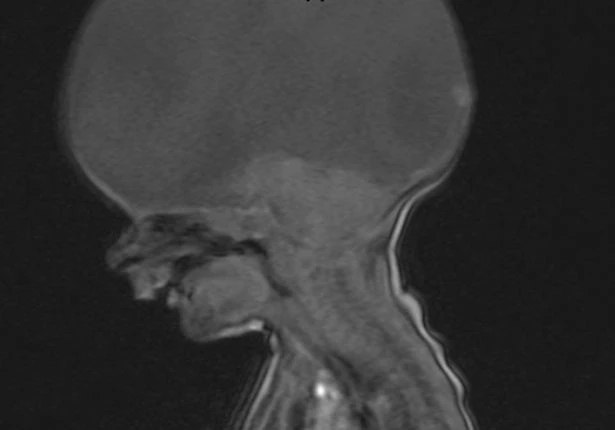

Cô Emma cho hay, kể từ khi được sinh ra, bé Aaron đã mắc dị tật hiếm khiến bé chỉ có phần cuống não. Các bác sĩ cho rằng bé chỉ có thể sống được 3 giờ cho đến 3 ngày sau khi chào đời bởi một dị tật hiếm có tên là holoprosencephaly .

Đây dị tật bẩm sinh ảnh hưởng đến não, xảy ra ở 1/10.000 ca sinh nở. Hầu hết các trường hợp mắc dị tật này đều tử vong trong bụng mẹ hoặc sau khi chào đời.